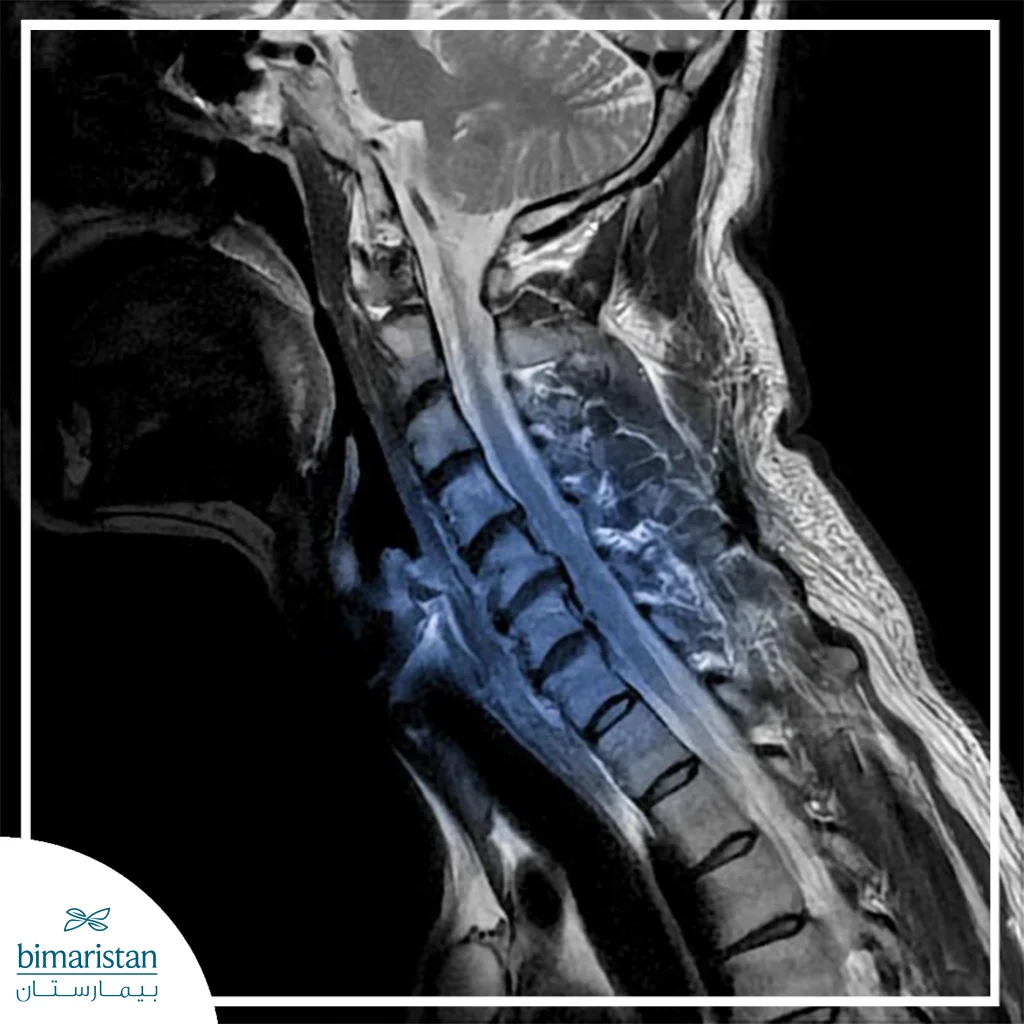

A neck disc is a slipped or eroded cartilaginous disc located between the vertebrae of the cervical spine. These discs act as cushions that absorb shock, protect the spinal cord, and help the neck move smoothly. However, when a disc weakens or protrudes, it can compress the nerve roots coming from the spinal cord. This compression may lead to pain in the neck or upper limbs.

A neck disc usually occurs as a result of multiple factors, such as prolonged sitting in the wrong posture, weakness of the muscles supporting the neck, and aging, which reduces the hydration and elasticity of the disc. Additionally, performing repetitive movements incorrectly can strain the discs. In some cases, sudden loading or direct injury may cause rupture of the outer layer of the disc, and symptoms of disc slipping may appear abruptly.